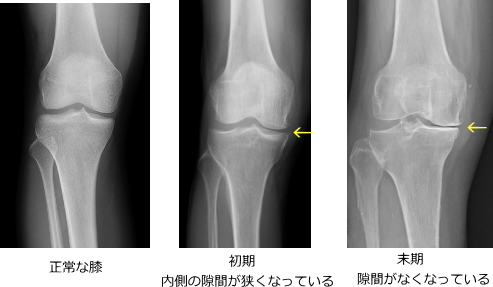

触診や可動域・腫脹の評価に加え、X線検査で診断します。軟骨自体は写りませんが、大腿骨と脛骨の関節裂隙の狭小化が所見となります。末期では骨同士の接触が見られます。